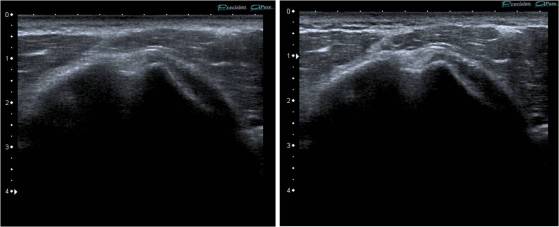

Imagen de alta frecuencia con y sin armónicos.

Las diferencias en algunos estudios son extremadamente llamativas, pudiendo llegar a diferenciar estructuras usando este ajuste que con la imagen fundamental se observan dificultosamente. En la imagen anterior, Tendón extensor común de los dedos de la mano. Misma imagen sin y con armónicos. Juzgar vosotros.

Observa las diferencias entre las dos imágenes.

En la imagen vemos dos imágenes, observamos que la nitidez y la definición de las estructuras es mucho mayor con armónicos que sin ellos.